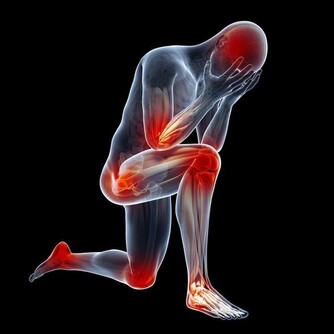

5.肢體麻木

患者常有明顯的手指麻木感,導致運動不靈敏。